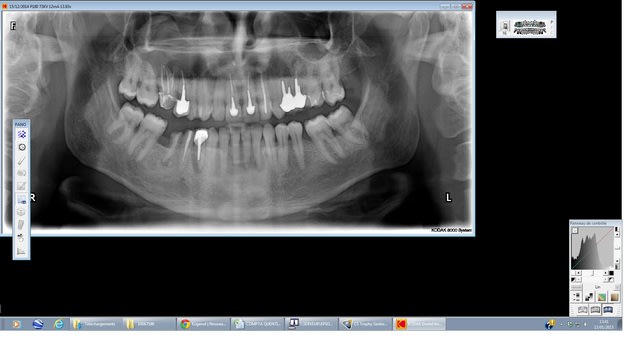

Perso ce qui me heurte dans la radio c'est la difference de volume entre les sinus droit et gauche.

Pas de coque du plancher sinusien visible sur les rx, à priori énorme destruction osseuse depuis 17 jusque 14, avec également masse radio dense grise de la taille d'une balle de ping pong mais de forme alongée.

J'ai bien peur devant le tableau que la notion de cancer ne soit pas facilement écartable, surtout si douleurs d'apparition rapides.

sur la première pano, on voit une grosse image radio claire de 17 à 14 a priori. ça serait intéressant de voir deux ou trois coupes du scanner ou le cone beam, mais je pense à un banal kyste d'origine dentaire très probablement en rapport avec la 16 d'autant que l'extension semble se faire en distal.

je viens de tel au radiologue: " le kyste est énorme et englobe 17 16 et 15, mais les corticales semblent préservées".